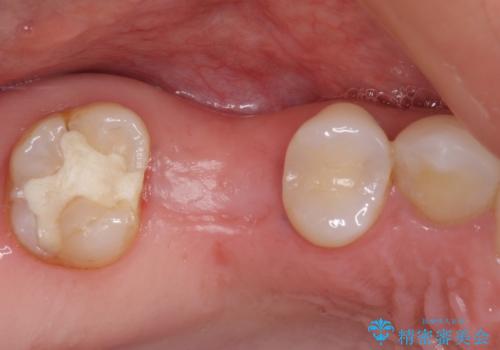

- 近医で奥歯の抜歯が必要であると指摘され、インプラント治療を希望して来院された患者様です。

診察の結果、大きな虫歯となっている歯は抜歯が望ましく、抜歯後にストローマンSLActiveを埋入することとしました。

さらに後方の歯は虫歯治療が途中であったため、ゴールドインレーにて修復治療行うこととしました。